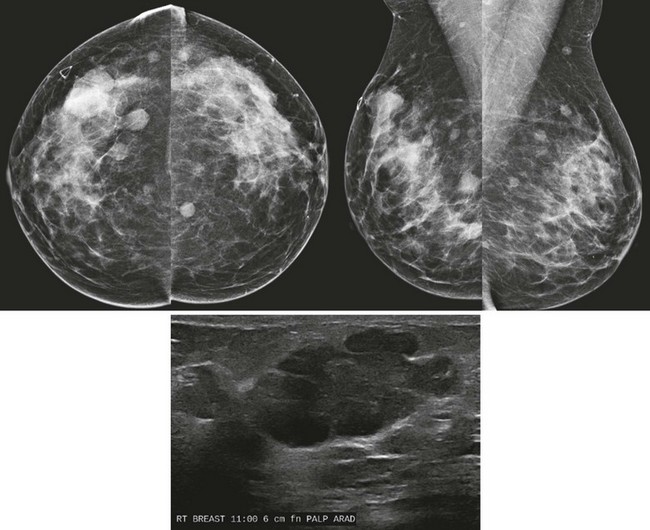

FIGURE 8-9 Waxing and Waning Cysts.

Some masses have enlarged while some have decreased in size. As long as the masses all have benign features and none are dramatically larger, recall is not necessary. This is BI-RADS 2.